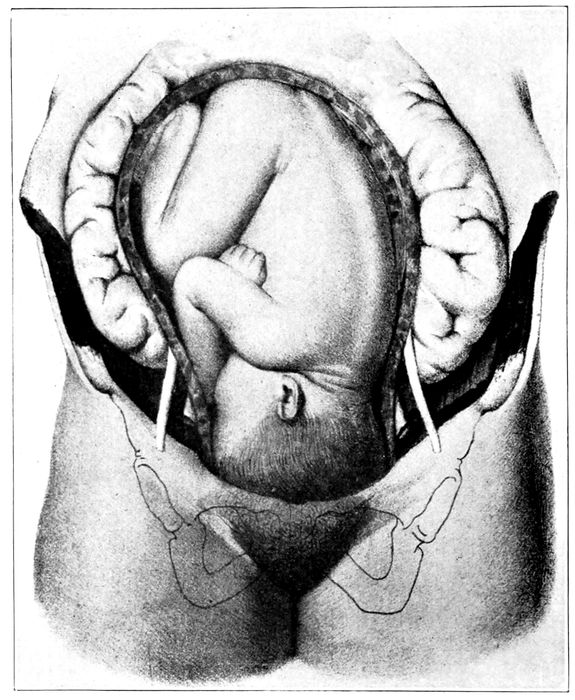

Fig. 19.—The egg at term with uterus removed and child showing through the membranes. (Edgar.)